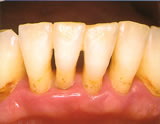

- 重度の歯周炎

歯茎の位置がかなり下がり、

歯の大部分が見えています。